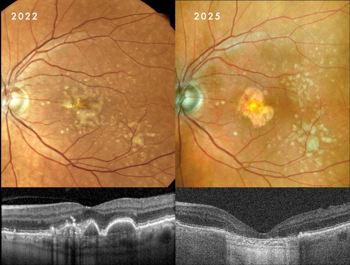

Clinical presentation: A 60-year-old woman presented with large, central drusenoid PEDs in both eyes. Natural history data indicate that the resolution of such lesions is almost invariably accompanied by atrophy of the underlying RPE and overlying photoreceptors.

Response to therapy: Following PBM, one eye exhibited a remarkable anatomical response: the PED resolved and flattened, accompanied by a significant restoration of the ellipsoid zone on OCT. Crucially, this occurred without the expected RPE atrophy (See Fig 1 at the top of this article).

This structural success was matched functionally, with BCVA improving from 6/9 to 6/6. In the fellow eye, the PED remained structurally stable, yet she still achieved functional gain, improving from 6/30 to 6/24.

Clinical implication: This outcome suggests PBM may facilitate the metabolic clearance of sub-RPE deposits while sustaining cellular viability, potentially altering the typical course of PED collapse. Further cycles of PBM treatment and longitudinal follow-up will determine if her fellow eye eventually achieves a similar anatomical resolution.

Clinical presentation: A 71-year-old man presented with a history of drusenoid PEDs first noted in 2022. Following discharge from public hospital services (reflecting the standard ‘watch and wait’ approach), he sought a referral for PBM after reviewing literature provided by MDNZ. Examination revealed that, since 2022, his PEDs had spontaneously resolved but, unlike Case 1, had progressed to moderate GA involving the foveal centre in both eyes.

Case 2, Fig 2. This demonstrates the typical natural history of drusenoid PED resolution. There was a relatively rapid change from no atrophy initially, to moderate geographic atrophy over a 3-year period